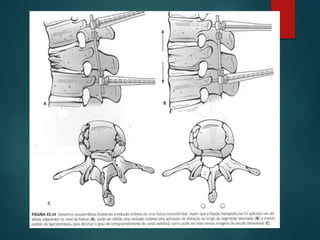

 A.3.1 – Fratura do tipo explosão

incompleta

 A.3.2 – Fratura do tipo explosão-

separação (burst-split) – Observar

a separação dos pedículos, a

cominuição da parte superior do

corpo vertebral e a separação da

parte inferior.

 A.3.3 – Fratura do tipo explosão

completa – Observar a separação

dos pedículos e a cominuição da

parte superior e inferior do corpo

vertebral.

 A.3.1 –Fratura do tipo explosão incompleta  A.3.2 – Fratura do tipo explosão- separação (burst-split) – Observar a separação dos pedículos, a cominuição da parte superior do corpo vertebral e a separação da parte inferior.  A.3.3 – Fratura do tipo explosão completa – Observar a separação dos pedículos e a cominuição da parte superior e inferior do corpo vertebral.